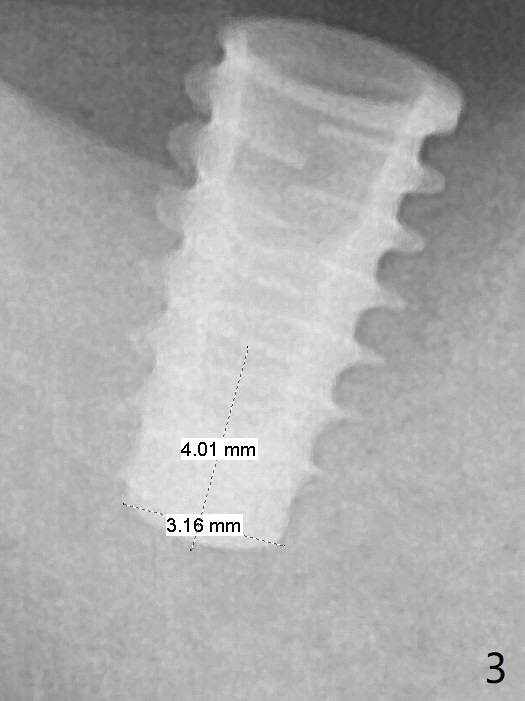

With pain and hemorrhage, the depth of osteotomy is unable to be achieved. Second the osteotomy is over prepared (Fig.3). Ideally after use of 2.8 mm round drill, a 4 or 4.5x9 mm dummy implant should be tried. In fact use of a shorter drill (4.3 mm in diameter) in Sinus Magic Kit with 4 mm stopper is a better match with the implant. When the implant becomes loose, use autogenous bone (before grinding) or Vanilla (.5-1.0 mm larger particles than Vera) may close osteotomy space.